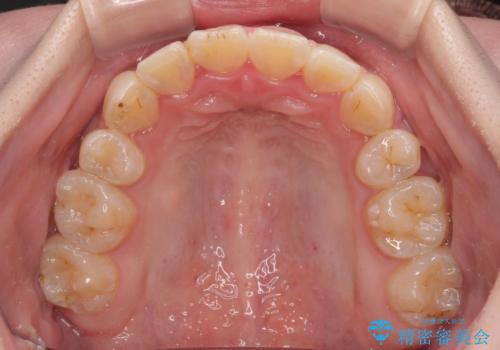

- 審美装置

- 八重歯や埋伏している奥歯など、多くの難しい問題を抱えている患者様です。

重度叢生のため、大臼歯をしっかりと咬合させるために、下顎は左右第二小臼歯を、上顎は前歯部の叢生を解消するために左右第一小臼歯を抜歯し、口元の突出感を改善するために、上顎大臼歯が前方に移動しないようにするために、補助装置による架強固定を行うこととしました。

叢生は思ったよりも早期に改善されましたが、舌の突出癖による上下前歯の非接触が全く改善されず、2年間ほど治療期間が延びる結果となってしまいました。